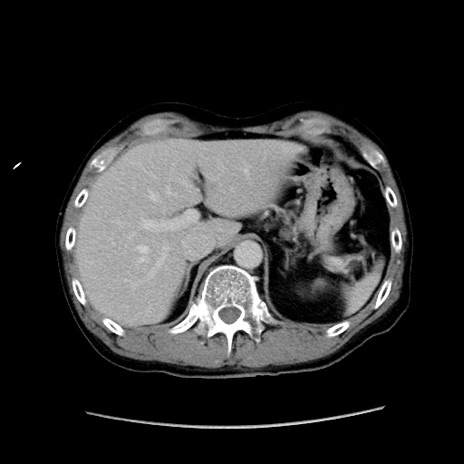

症例37(横断像)

【症例】40歳代 男性

【主訴】腹痛

【現病歴】4時間ほど前に電車に乗車中に臍部上より腹痛出現。徐々に増悪し起立困難となり、救急外来受診。生ものは数日食べていない。今朝お雑煮を食べた。

【身体所見】BT 36.8℃、BP 117/84mmHg、HR 91/min、SpO2 97%、苦悶様、腹部:臍上部広範囲圧痛あり、反跳痛±

【データ】WBC 8100、CRP 0.03